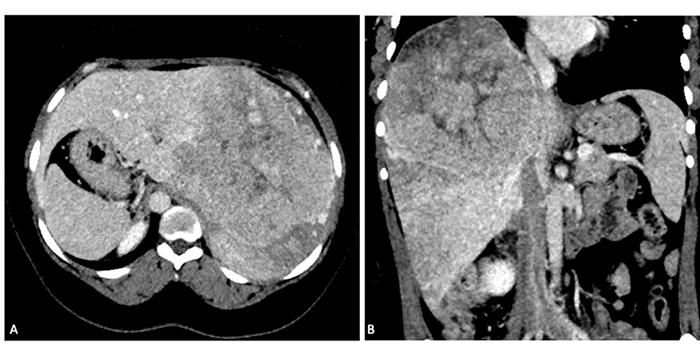

Intraoperative ultrasound revealed minimal fibrosis in the left lobe, without gross cirrhosis, which was confirmed by surgical biopsy of the left lateral segment. Notably, after liver mobilization, an inferior right hepatic vein (iRHV) draining segment six directly into the inferior vena cava (IVC) was identified (Figure 2). This was not visualized on preoperative imaging due to significant tumor compression. The tumor involved segments 7, 8, 5, 4A, and 4B, but segment 6 was spared despite preoperative imaging suggesting significant perfusion abnormality in this segment.

Figure 2. Preoperative CT Scan Depicting Mass Effect and Perfusion Anomaly. Published with Permission

(A) Axial view demonstrating significant tumor compression, mass effect, and perfusion anomaly in segment 6, along with a perfusion defect in the inferior vena cava. (B) Coronal view highlighting the same findings